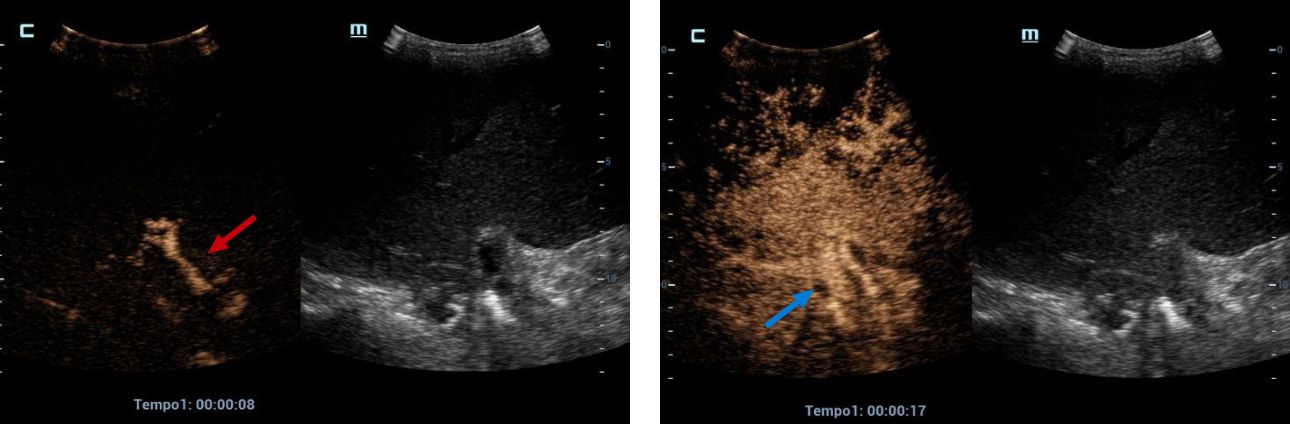

CEUS, an earlier than expected enhancement of vascular structures is observed, the artery phase begins at 8 seconds (red arrow) and the portal/venous phase at 17 seconds (blue arrow).

Figures 2 and 3. CEUS, an earlier than expected enhancement of vascular structures is observed, the artery phase begins at 8 seconds (red arrow) and the portal/venous phase at 17 seconds (blue arrow).